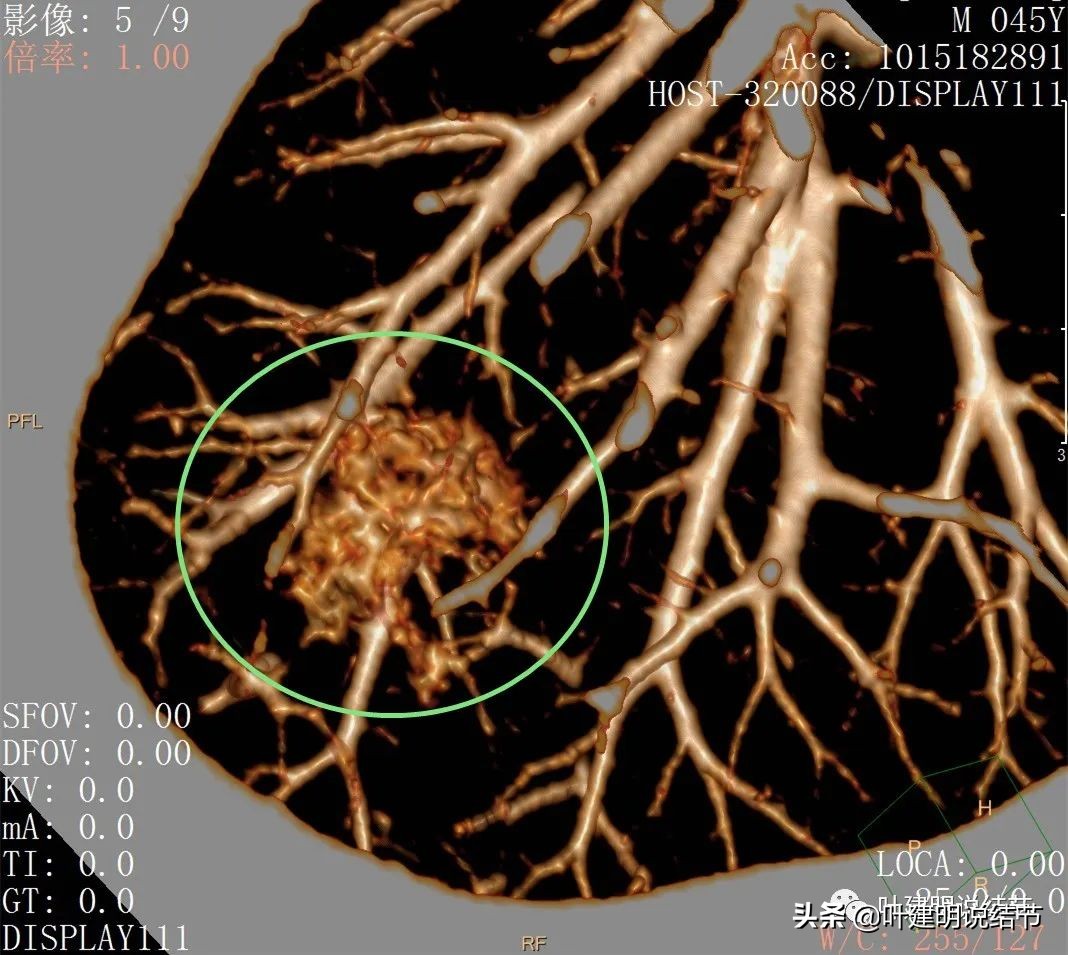

后处理影像:

血管征明显,从不同角度与方向进入,并在病灶内增粗

三维重建看病灶整体还是类圆形的,只是有的方向延伸出去而已,与血管关系密切。